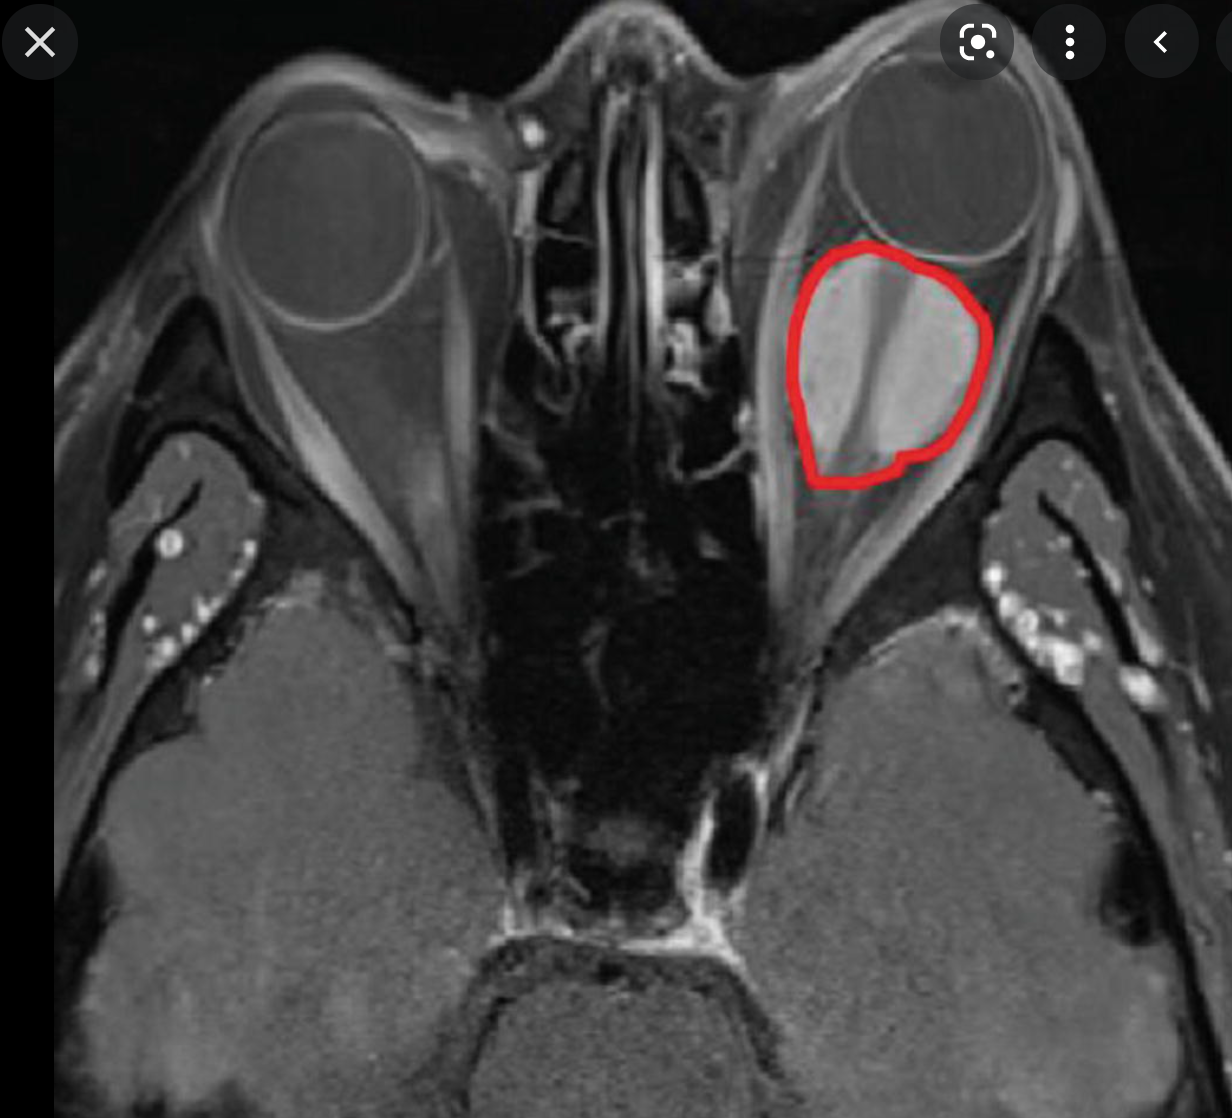

Orbital hemangiopericytoma